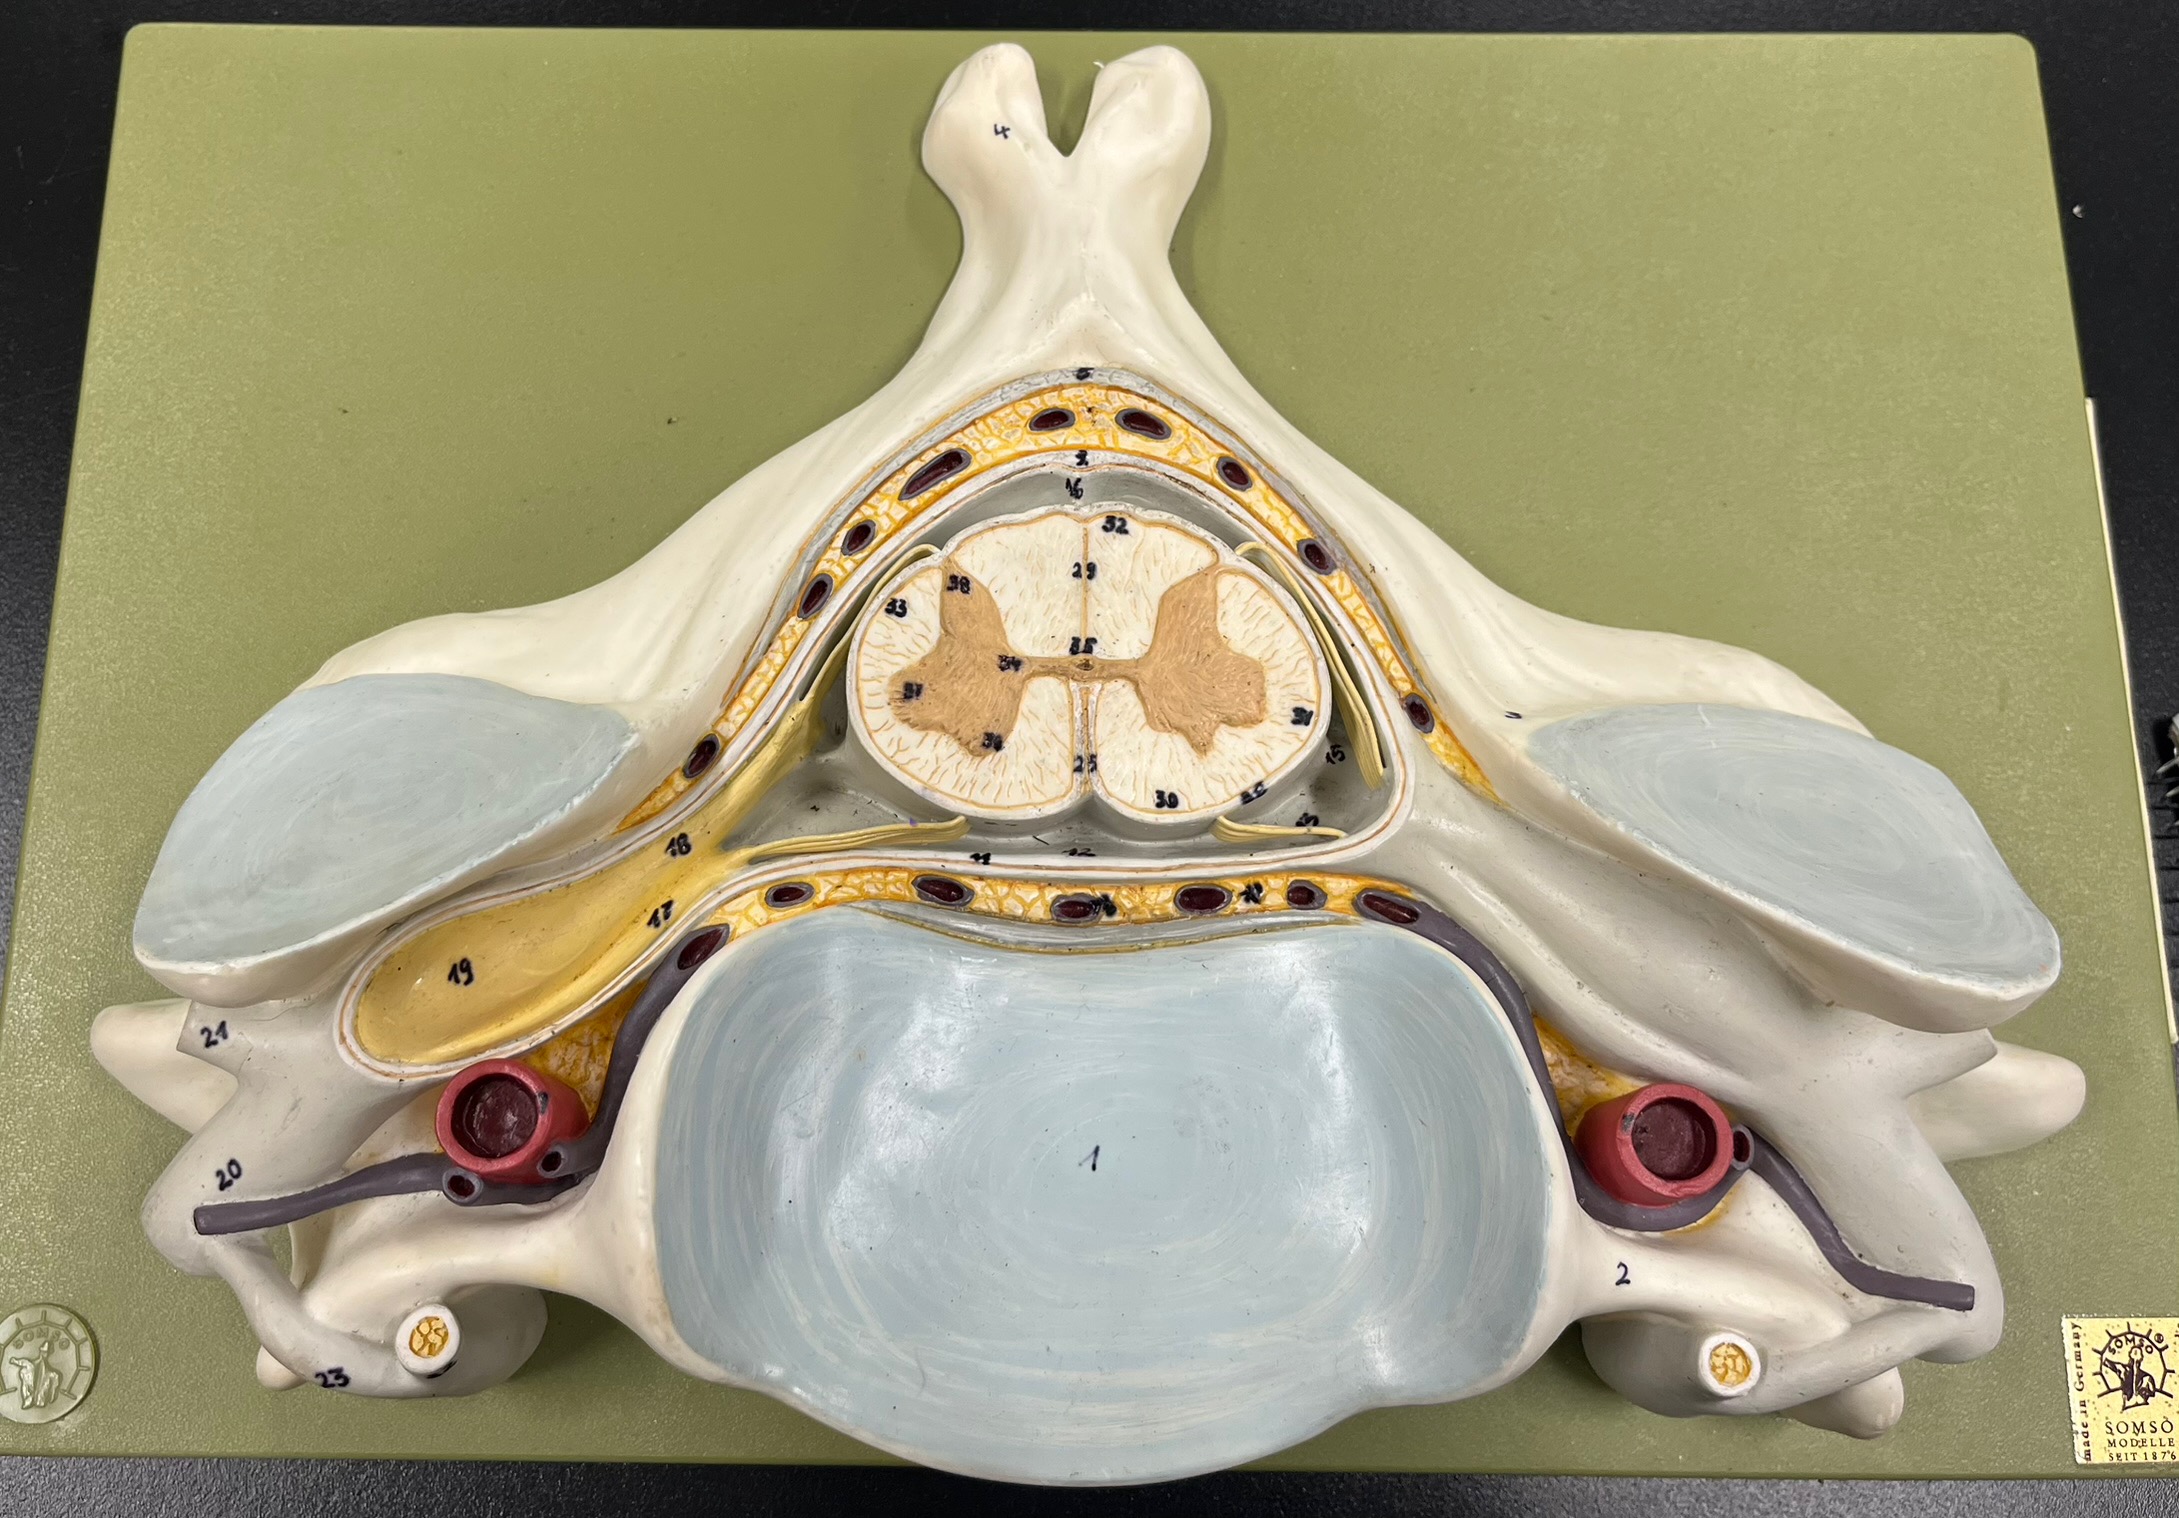

epidural space

dura mater

subdural space

arachnoid mater

subarachnoid space

pia mater

denticulate ligaments

What is the groove here?

anterior median fissure

posterior median sulcus

posterior (dorsal) horn

posterior (dorsal) horn; R—>L

anterior (ventral) horn

lateral horn (selected models)

gray commissure

central canal

anterior column

lateral column

posterior column

white commissure

posterior (dorsal) root ganglion

What is the bulb here?

posterior (dorsal) root ganglion

posterior (dorsal) root

posterior (dorsal) root

anterior (ventral) root

anterior (ventral) root

dorsal ramus

dorsal ramus

ventral ramus

ventral ramus

rami communicantes

rami communicantes

sympathetic chain ganglia

sympathetic chain ganglia